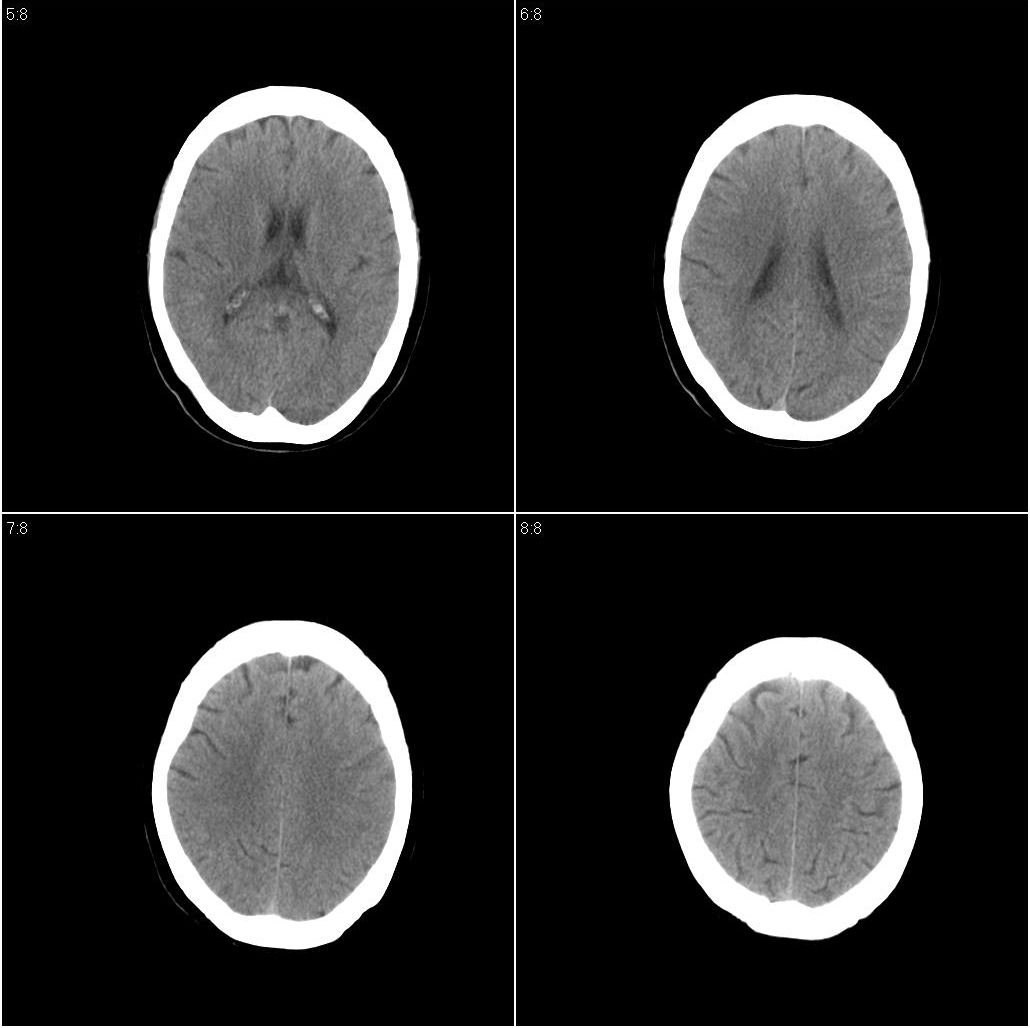

以下是引用欧阳双全在2008-6-5 16:37:00的发言:[br]小类圆形低密度影,边界清,考虑为外囊区腔隙性脑梗塞!

以下是引用zjzjr在2008-6-5 17:32:00的发言:[br]右侧基底节腔隙性梗塞!